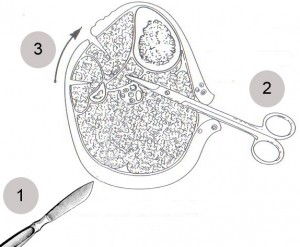

Техника проведения дренирующих операций.

Рис. 2. Схематичное изображение поперечного среза голени в средней 1/3 и этапы выполнения дренирующей операции:

- 1- рассечение кожи преимущественно по латеральным осевым линиям (рис. 3), планирование разрезов с учетом локализаций на конечностях

(схемы на рис. 3-6);

- 2- рассечение фасции, проведение расслоения мышечных тканей браншами ножниц, визуализация степени ишемизации тканей с последующим дренированием каждого компартмента (по показаниям);

- 3- смещение рассеченной кожи с подкожной клетчаткой для проведения следующей фасциофенестротомии и визуализации других компартментов.

Анатомия мышечных влагалищ (отсеков – компартментов) подробно описана в руководствах по анатомии человека [8,9].